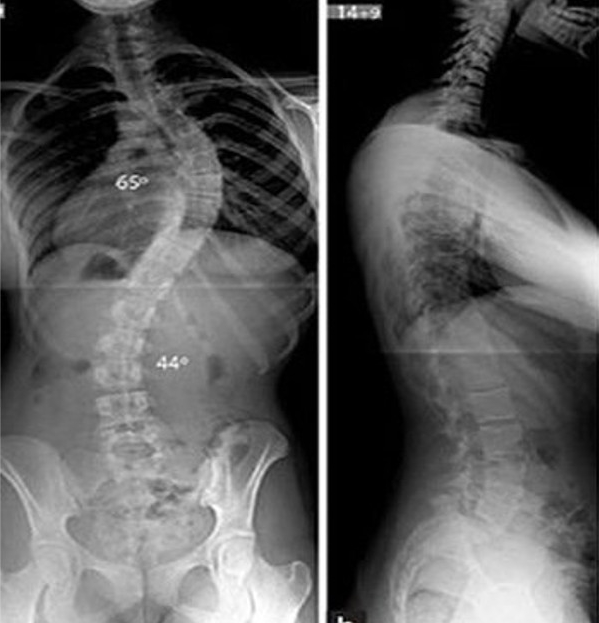

Để chẩn đoán vẹo cột sống, chụp Xquang là biện pháp tốt nhất chẩn đoán vẹo cột sống. Xquang phải đảm bảo lấy được toàn bộ cột sống.

| Hình ảnh X-Quang vẹo cột sống |